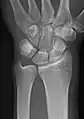

- Wrist - DP and Lateral

Left wrist by dorsoplantar projection

Lateral projection